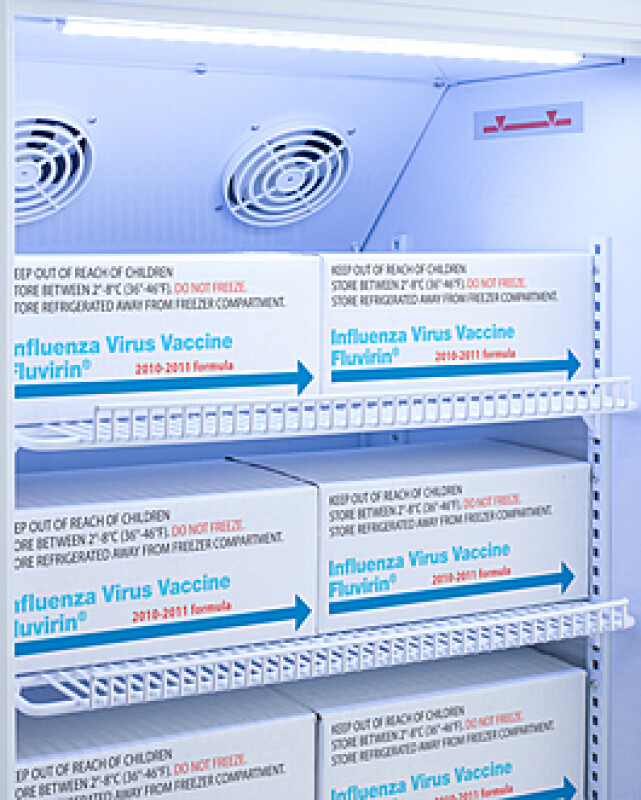

3 Cu.Ft. Counter Height Vaccine Refrigerator - ARS3PVDL2B

Purpose-built design

Adjustable plastic-coated wire shelves for improved circulation

Interior light

| Capacity | 3.0 cu.ft. (85 L) |

| Shelf Qty | 4 |

| Adjustable Shelves | Yes |

| Fan Type | Interior |

| Temperature Range | 2 to 8ºC |